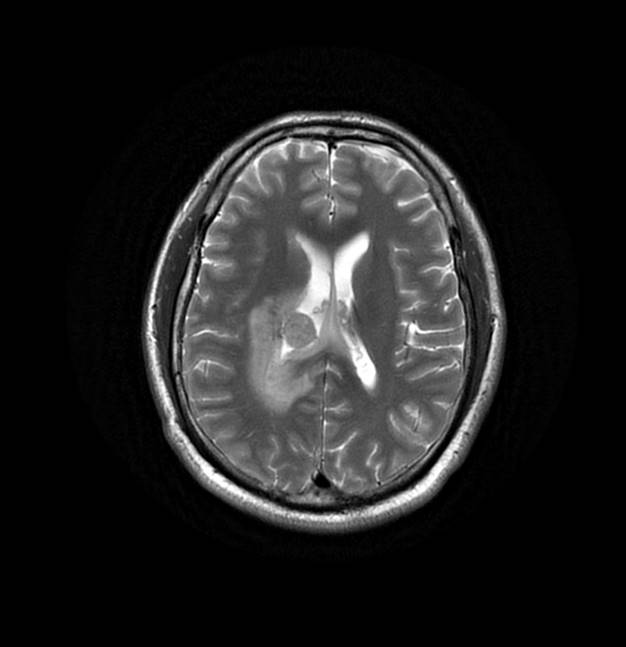

磁共振影像圖

圖2

MR診斷:右側(cè)側(cè)腦室三角區(qū)及側(cè)腦室旁占位,考慮惡性腫瘤可能,間變型腦膜瘤?轉(zhuǎn)移瘤?

MR鑒別診斷

常規(guī)MR檢查是診斷腦膜瘤的有效手段,可以明確腫瘤發(fā)生的部位、形態(tài)和數(shù)目等特征以及病變向鄰近腦實質(zhì)侵犯的程度和范圍,典型腦膜瘤呈等或(和)稍長T1、等或(和)稍長T2信號,??娠@示完整的包膜,增強掃描因腫瘤內(nèi)部新生血管通透性不同呈不同程度強化,由于腫瘤組織的強化程度與腫瘤的惡性程度不完全一致,導致MR常規(guī)檢查在腦膜瘤分級分型方面仍存在一定的困難。擴散加權成像( diffusion weighted imaging,DWI) 及表觀擴散系數(shù)( apparent diffusion coefficient,ADC) 被廣泛用于腦腫瘤的分級、分子分型和腫瘤侵襲性預測,并取得了良好的性能。目前,對于非典型腦膜瘤腦實質(zhì)侵犯的診斷的金標準依賴于組織病理學。